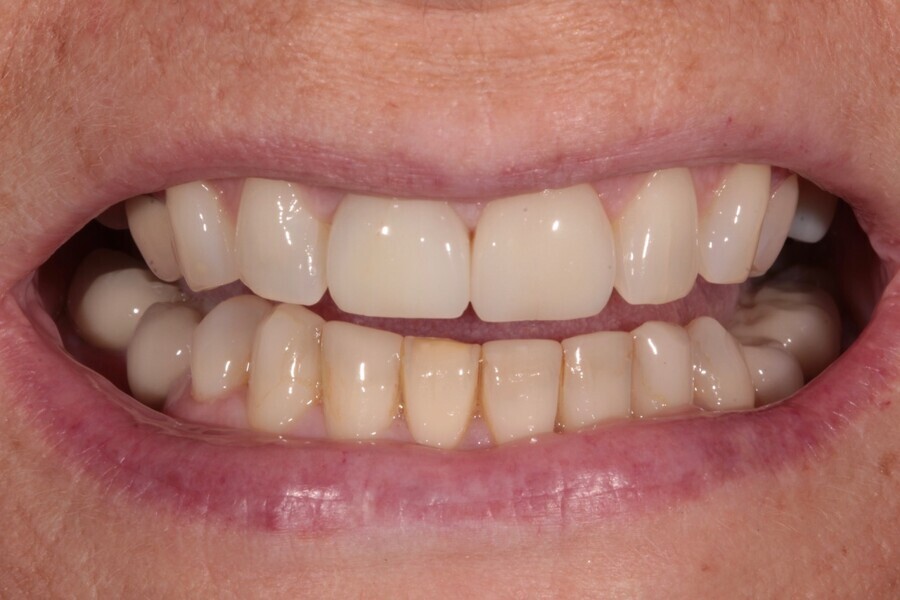

In 2021, the patient decided to have the two maxillary central incisor restorations replaced with a lithium disilicate crown and veneer (Fig. 13). The maxillary palatal platforms created with Venus Diamond in 2017 were still functional, and the repaired mandibular central incisal edge was still intact (Figs. 14 & 15). The original edge bonding on the other mandibular teeth still remained in place, 17 years later.

To enhance the mandibular canines and incisors, the teeth were polished with the simple-to-use and predictable Venus Supra polishing kit (Kulzer). However, it is likely that in the next two to three years they will all be replaced with Venus Diamond composite.

This case effectively demonstrates that the concept of “pausative” dentistry can be aesthetic, functional and affordable. If this patient’s teeth had been left untreated from 2004, how would they have looked 17 years later? The mandibular crowding would likely have worsened.2 The bite would probably have deepened, causing more surface loss, as there were already signs of dentine exposure. The already reduced posterior guidance would likely have worsened and more posterior teeth may have failed.

The “pausative” approach with alignment and direct edge bonding according to the Dahl principle can help to minimise the amount of damage in long-term cases (Fig. 16). It can help prevent further tooth surface loss and tooth positional changes and hold the occlusion in a much better position over time.

Fig. 16: 2021—the patient’s teeth 17 years later thanks to interceptive treatment with alignment and direct edge bonding according to the Dahl principle to minimise the amount of damage.